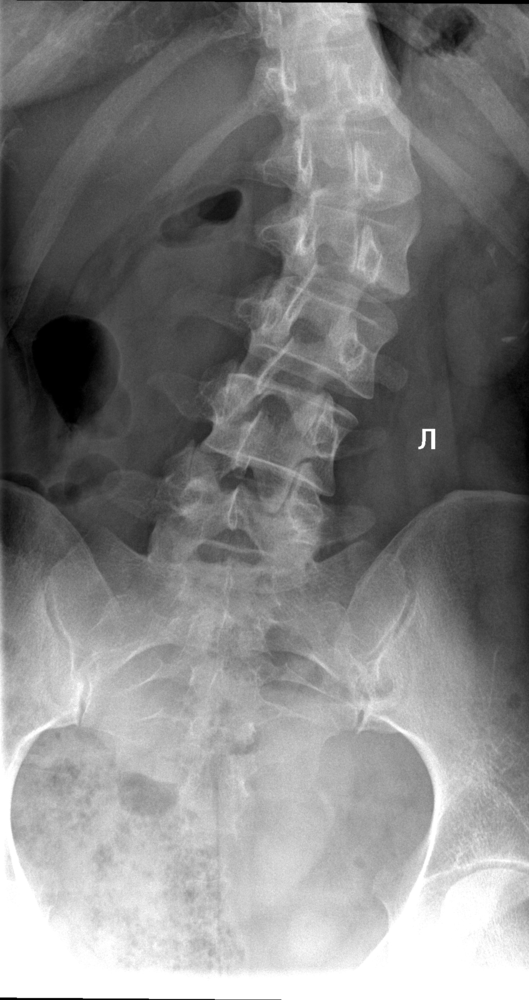

Coloana vertebrală. Scolioza

Scolioza este o deviație laterală a coloanei vertebrale.